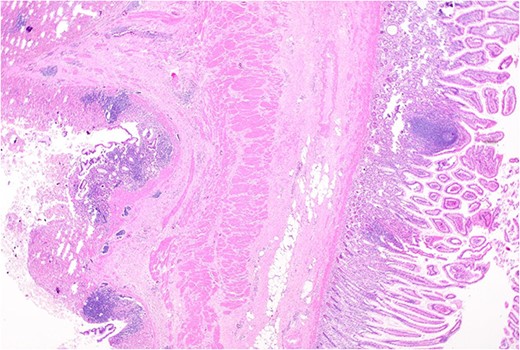

Histopathology macroscopically identified a 42-mm cystic caecal mass adjacent to the ileocaecal valve (Figs 4–5). Microscopic examination revealed a duplication cyst involving the ileal and colonic tissue comprised of a complete duplication of the colonic wall including mucosa, submucosa and muscularis propria, which was shared with the involved colon (Fig. 6). There was no mucosal connection to adjacent normal bowel. There was some ulceration with inflammatory changes in the overlying mucosa suggestive of prior cyst perforation and areas of attenuated villiform mucinous epithelium with features of low grade dysplasia (Figs 7-8). Special stains for organisms (Periodic Acid-Schiff (PAS), Fredericamycin A (FMA), Ziehl-Neelsen (ZN) and modified ZN) were negative. There were no granulomas, heterotopic mucosa or evidence of malignancy. Twenty-nine lymph nodes were identified with no evidence of malignancy.

Remnant of normal colonic epithelium (left) within the duplication cyst that shares common muscularis propria with the terminal ileum (right), low power.

Area of dysplastic mucosa (right) within the duplication cyst that shares a common wall with the right colon (left), low power.